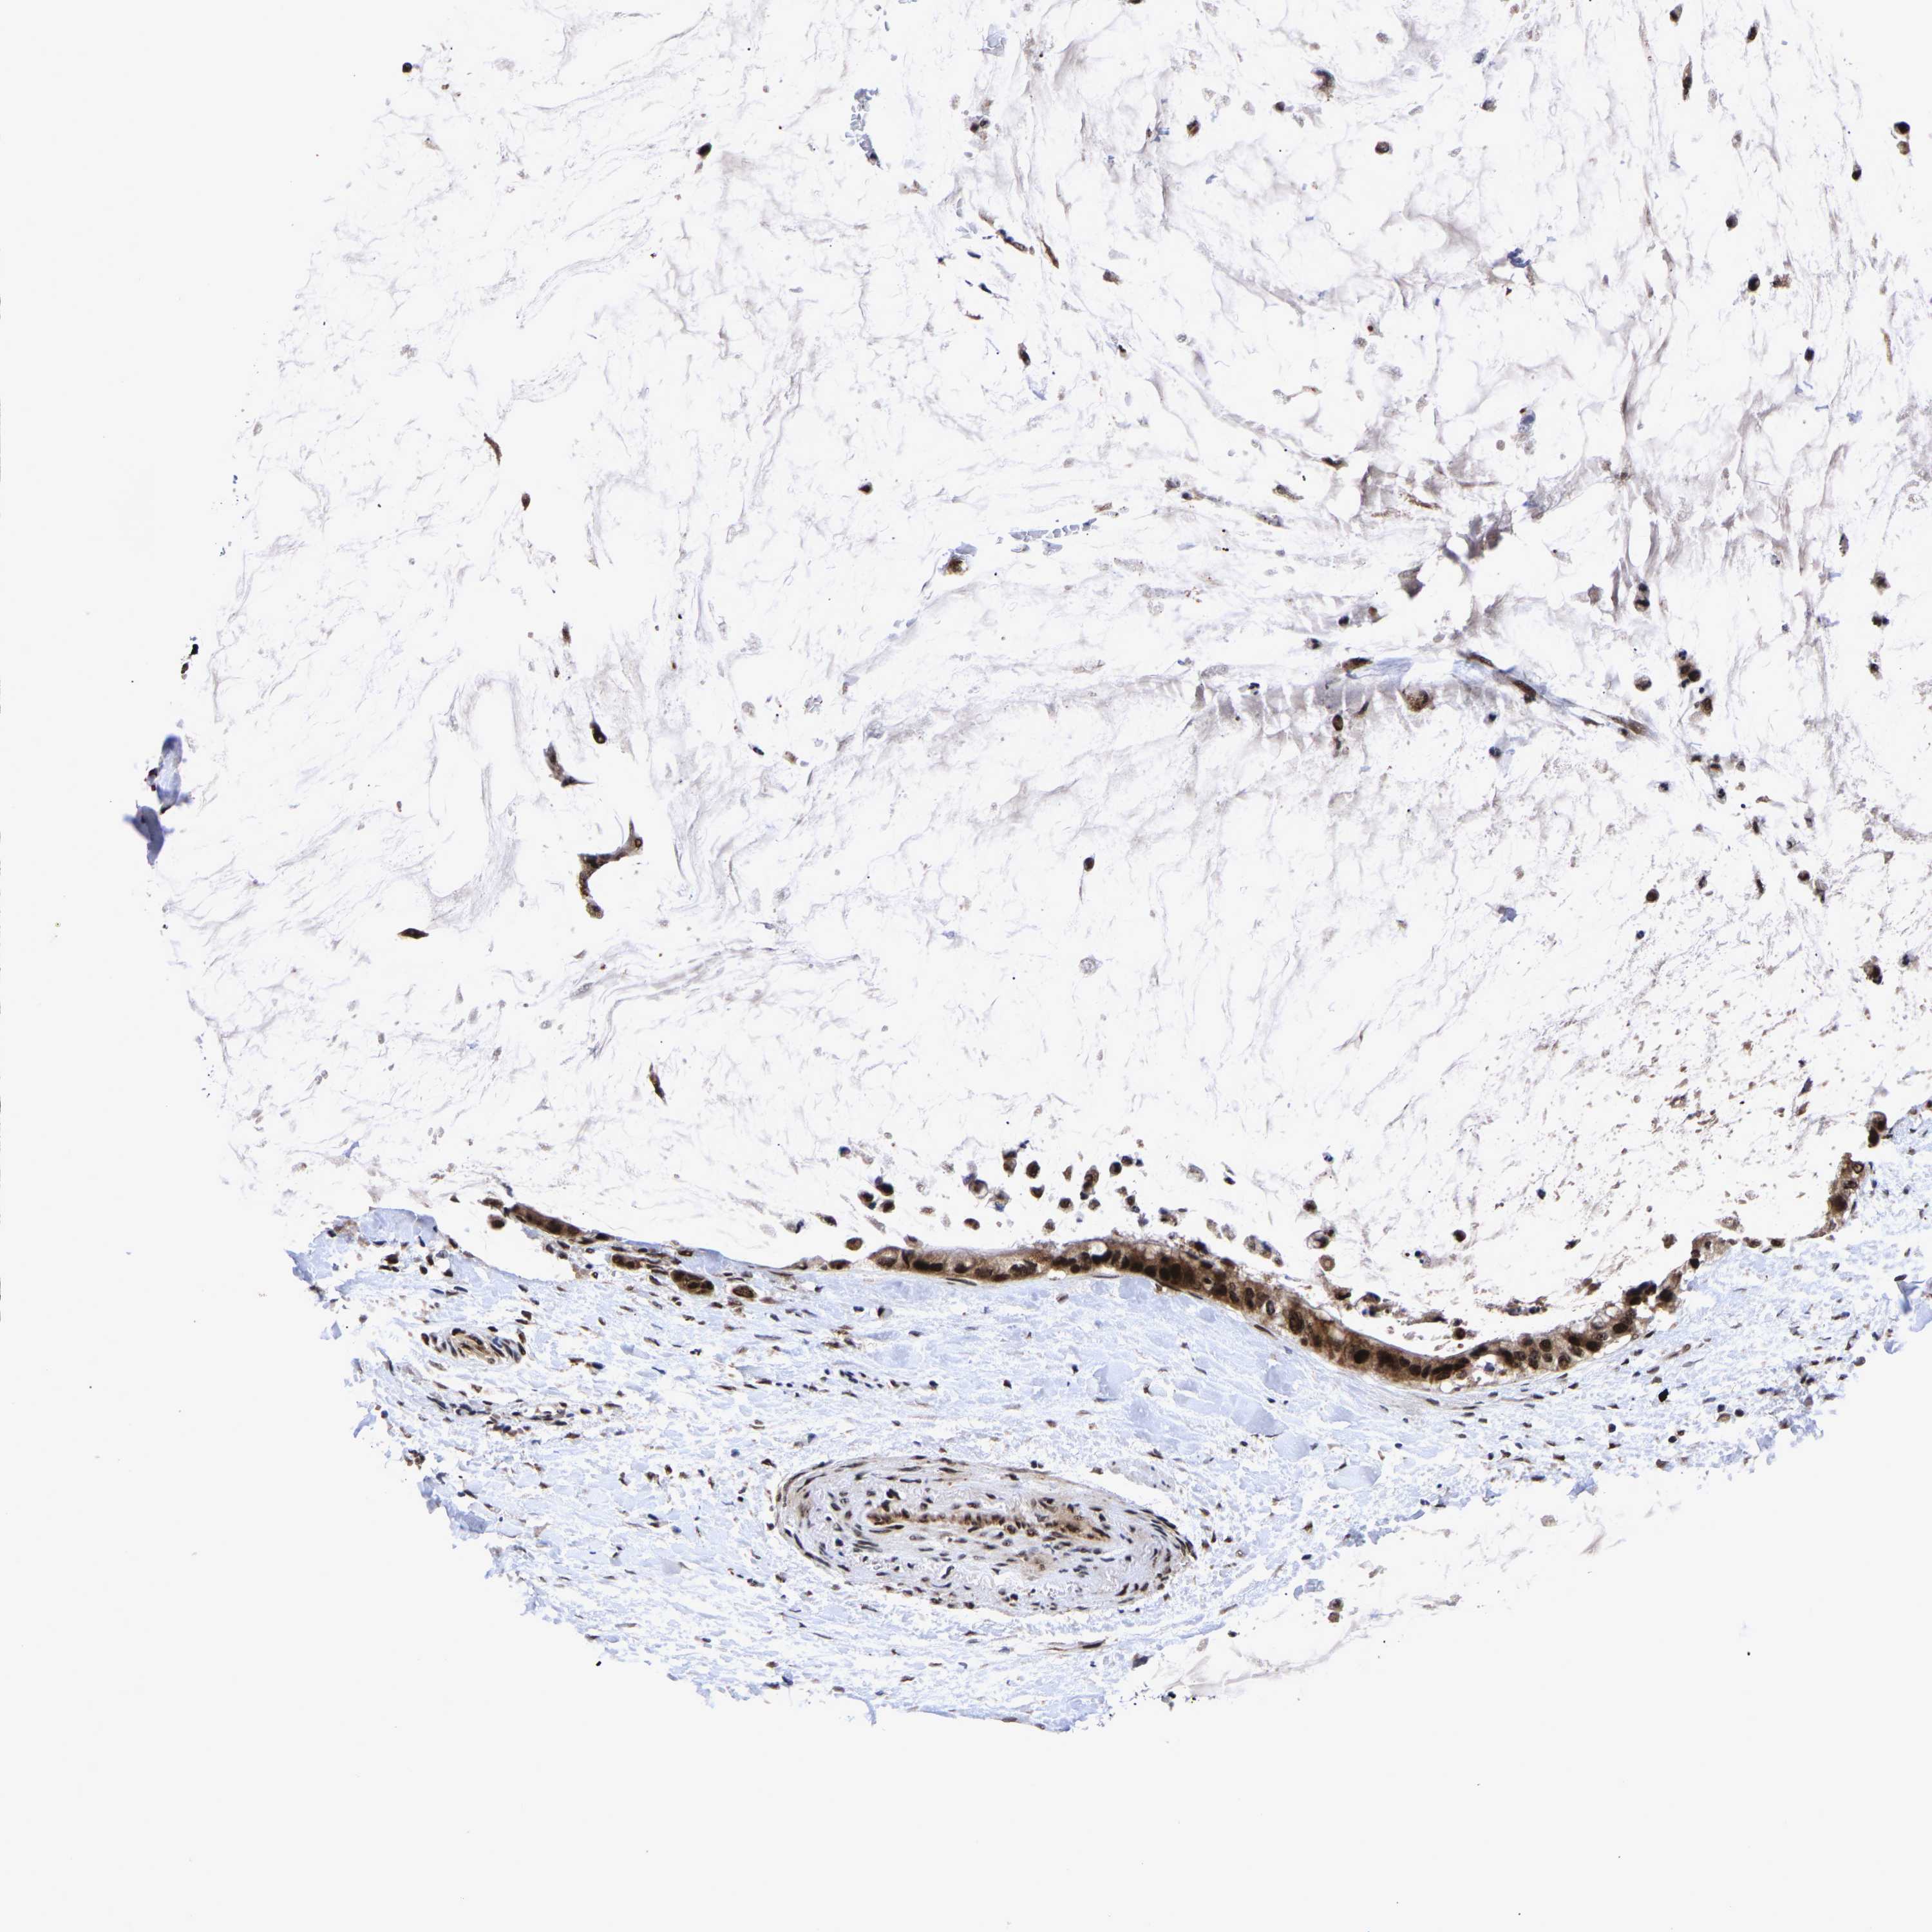

PANCREATIC CANCER - Protein expressioni

A mouse-over function shows sample information and annotation data. Click on an image to view it in a full screen mode. Samples can be filtered based on level of antibody staining by selecting one or several of the following categories: high, medium, low and not detected. The assay and annotation is described here.

Note that samples used for immunohistochemistry by the Human Protein Atlas do not correspond to samples in the TCGA dataset.

Antibody stainingi

Antibody staining in the annotated cell types in the current human tissue is reported as not detected, low, medium, or high, based on conventional immunohistochemistry profiling in selected tissues. This score is based on the combination of the staining intensity and fraction of stained cells.

Each image is clickable and will lead to virtual microscopy that enables deeper exploration of all samples and also displays staining intensity scores, fraction scores and subcellular localization as well as patient and tissue information for each sample.

Antibody HPA019149

Antibody CAB004464

Staining

High

Medium

Low

Not detected

Intensity

Strong

Moderate

Weak

Negative

Quantity

>75%

75%-25%

<25%

None

Location

Nuclear

Cytoplasmic/membranous

Cytoplasmic/membranous,nuclear

Adenocarcinoma, NOS

Adenocarcinoma, metastatic, NOS